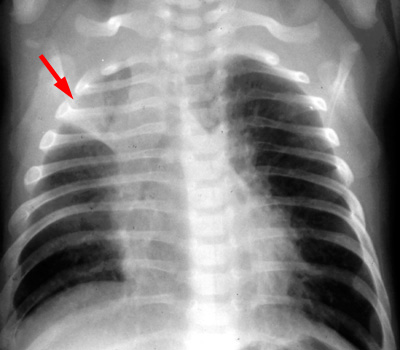

Bronchitis will manifest on the CXR as peribronchial thickening or "peribronchial cuffing". A bronchus seen on end will show the bronchial wall thickening, and the hilum will demonstrate a dirty appearance, which is well demonstrated on the lateral projection.

PA CXR demonstrates atelectasis. |